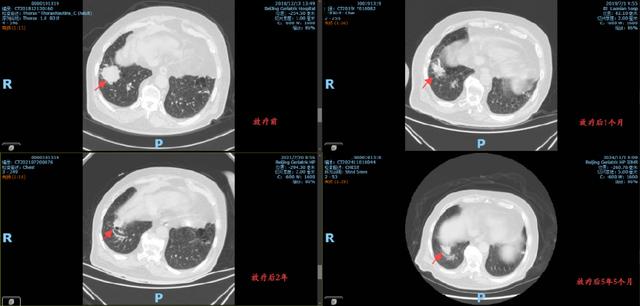

放疗后的复查显示,李大爷右肺下叶的病灶明显缩小,血氧水平得到改善,身体状况显著提升。更令人欣慰的是,自2019年以来,李大爷的病灶未再出现进展,五年随访中始终保持稳定。

从2019年4月至5月,李大爷接受了共30次精准放疗。治疗过程顺利,期间无明显不良反应。放疗团队通过实时影像引导技术,确保每次治疗都精准靶向病灶区域,力求既达到局部控制效果,又避免损伤周围正常组织。